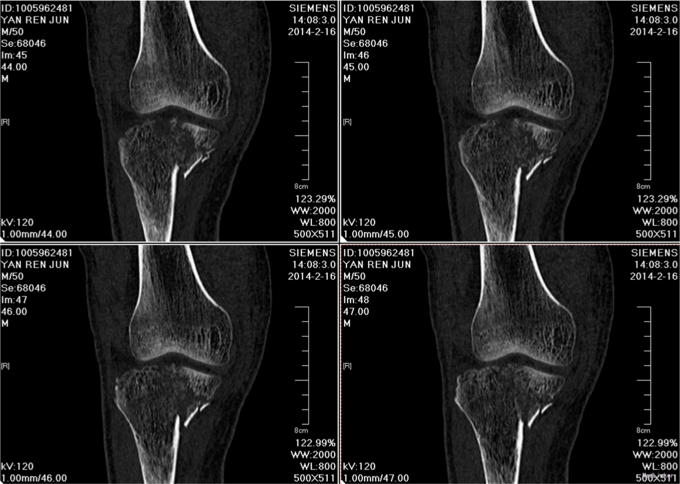

主诉:摔伤后右膝关节疼痛伴活动受限5小时。 该患于2014.2.14骑车摔伤,伤及右膝,伤后局部肿胀,疼痛,活动受限。于沈阳市骨科医院就诊,右膝关节DR片示右胫骨平台骨折、右胫骨骨折后为求进一步诊治故来我院,门诊行相关检查后以"右胫骨平台骨折、右胫骨骨折"收住我科。伤后无意识障碍,无视物不清,无头晕、头痛,无恶心、呕吐,无二便失禁,无胸闷及呼吸困难,无腹胀、腹痛。

诊断:左胫骨平台骨折(SchatzkerⅣ型) 患者入院后见患肢肿胀明显,给予患肢抬高位,冷敷,甘露醇消肿等对症治疗,带患肢出现褶皱试验阳性后,全麻下行左胫骨平台骨折切口复位钢板内固定术,术后患者肿胀明显,给予抗炎,消肿,冷敷,患肢抬高等对症治疗。患者每天换药观察切口愈合情况,无红肿及渗出,待伤口14天后予以拆线治疗,予以出院,给予康复处方。